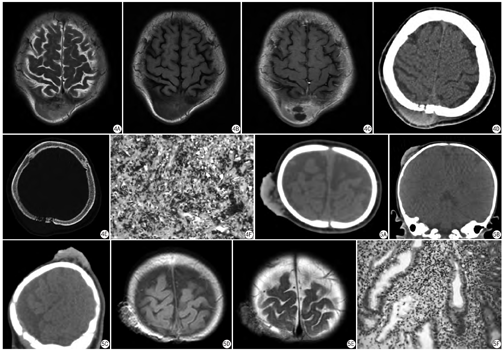

影像表现分析:在本研究中,每例病例均由2名具有5年以上临床诊断经验的放射科影像医师独立观察图像,分析病变的病灶数目(单发或多发)、形态是否规整、密度或信号是否均匀、有无钙化、脂肪成分、是否存在坏死及分隔、观察邻近颅骨是否破坏、是否侵犯颅内组织,判断病灶良恶性并做出最终诊断,根据病理结果并参照文献[17]对病灶按组织来源进行分类。最终诊断结果必须经2名影像医师共同协商一致后方能列入后续研究。当两位主要影像医师意见分歧时,咨询第3名影像专家,最后做出最终诊断结果(图1,图2,图3,图4,图5)。

本组病例最大者最大横截面积可达90 mm×52 mm,最小者约3 mm×3 mm,平均横截面积约358 mm2。按病灶密度分类可将本组病例分为以脂肪密度为主病变(如脂肪瘤),平均CT值约为-83 Hu;以钙化密度为主的病变(钙化上皮瘤),平均CT值约为272 Hu,其余病变均以软组织密度为主,平均CT值约为46 Hu。

本组病例行超声检查84例,CT171例,MR80例,23例行增强扫描检查,其中CT增强3例,MR增强成像20例。经病理证实,超声正确诊断57例,CT正确诊断146例,MRI正确诊断73例;良性病例超声正确诊断率为70.5%,CT检查正确诊断率为88.6%,MRI检查正确诊断率为94.4%;恶性病例超声正确诊断率为33.3%,CT检查正确诊断率为46.2%,MRI检查正确诊断率为62.5%。良、恶性病变的不同影像检查方法确诊率比较如图7所示。增强扫描检查后正确诊断19例,误诊4例,增强检查的正确诊断率为82.6%。

某些头皮占位性病变可有特征性影像表现,并能够提出相应组织学诊断,如钙化上皮瘤内可见特征性钙化密度灶;脂肪瘤CT值为负值最具有特征性。但绝大多数头皮占位病变的良恶性鉴别诊断一直是临床及影像检查工作的重点及难点,临床医师除依据疾病的好发部位、好发人群、临床症状表现外,特征性的影像表现征象,如病灶大小、密度、病灶数目、形态及病灶内成分的多样性往往能够提示病变的良、恶性。本研究利用ROC曲线对头皮占位性病变的最大横截面积和病灶密度进行分析,病灶最大横截面积的ROC曲线下面积(area under curve,AUC)为0.748,临界值为234 mm2,诊断灵敏度及特异度分别为83.33%、64.26%,具有统计学差异(P <0.05),说明病灶大小可作为鉴别头皮占良恶性的诊断指标,且当病灶最大横截面积大于248 mm 2时,需考虑恶性病变可能。病灶平均密度AUC为0.516,无统计学差异(P>0.05),因此认为病灶密度对鉴别头皮占位的良恶性作用不大。

影像检查是头皮占位性病变的重要术前检查手段,系统全面的影像检查不仅能降低病变的漏诊率,还能大大提高病变的诊断率。不同的影像学检查具有各自的优势,超声检查价格较低,患者普遍接受度好,可用于筛查;CT及MR对病变的定位及定性具有重要价值[24]:CT具有高密度分辨率,对骨组织、软组织骨化、钙化显示清晰、敏感,可清楚地显示病灶对颅骨的破坏,CT薄层三维重建及后处理更有利于全面观察病变的形态及大小[25];MRI扫描具有多个序列可供选择,对于病灶内部成分构造敏感度高,具有很高的鉴别诊断价值。另外MRI检查对病变周围血管、神经情况以及病灶侵袭范围程度更加敏感,能够更加早期地判断疾病进程,可作为头皮占位诊断的首选检查方法[26,27]。

本组病例超声检查、CT、MR检查的正确诊断率依次增高,MRI检查对头皮良性占位的正确诊断率可高达94.4%,对恶性病变的正确诊断率高达62.5%。不同影像检查手段相辅相成、各有优势,超声、CT、MR可逐渐补充、提高病变诊断率,MRI对病变具有较高的诊断价值因而可作为头皮占位性病变的首选检查方法;本组病例增强扫描检查对诊断头皮占位性病变的确诊率为85.7%,诊断灵敏度为66.7%,特异度88.9%,因此,在确定病变良恶性具有一定困难时,增强扫描也可以作为诊断头皮占位性病变、鉴别病灶良恶性的一种重要补充检查方法。